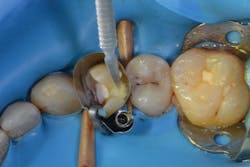

Figure 7: After thoroughly rinsing the etchant away, Prime&Bond Elect is scrubbed into the preparation for 20 seconds.

In this case, phosphoric acid was first applied to the margins of the preparation and then used to fill in the entire cavity (figure 6). After 15 seconds, the gel etchant was rinsed away and the preparation was left slightly moist. Prime&Bond Elect was scrubbed over the entire preparation, air-thinned for five seconds, and light cured for 10 seconds (figure 7). A bulk-fill flowable composite base was placed, followed by a hybrid composite restorative to fill the cavity per the manufacturer’s recommendations. The matrix and rubber dam were removed. After we checked occlusion and finished the restoration to achieve a smooth final surface, the patient was released (figure 8).